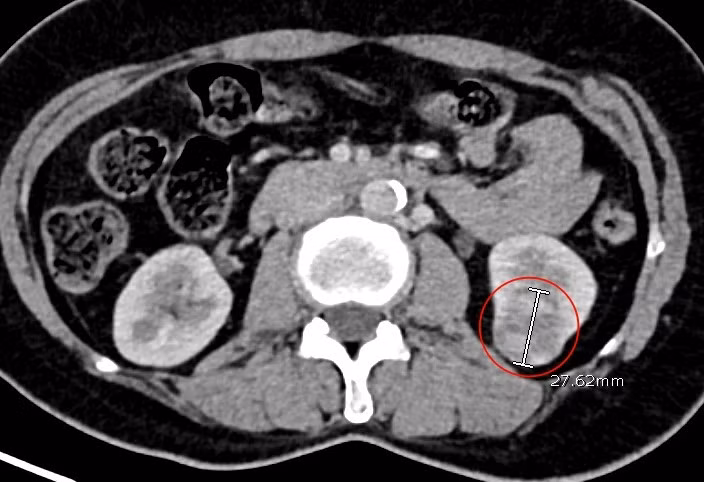

| Hình ảnh khối u thận ác tính của bệnh nhân Ph. qua phim chụp cắt lớp vi tính - Ảnh BVCC |

Kết quả siêu âm phát hiện u thận trái kích thước gần 30 mm, được chỉ định chụp cắt lớp vi tính xác định bản chất u. Hội chẩn đánh giá đây là ung thư tế bào thận trái, giai đoạn sớm còn khu trú trong thận, chưa xâm lấn di căn, vì vậy các bác sĩ chỉ định phẫu thuật nội soi cắt thận bán phần, giúp người bệnh thoát khỏi căn bệnh hiểm nghèo.